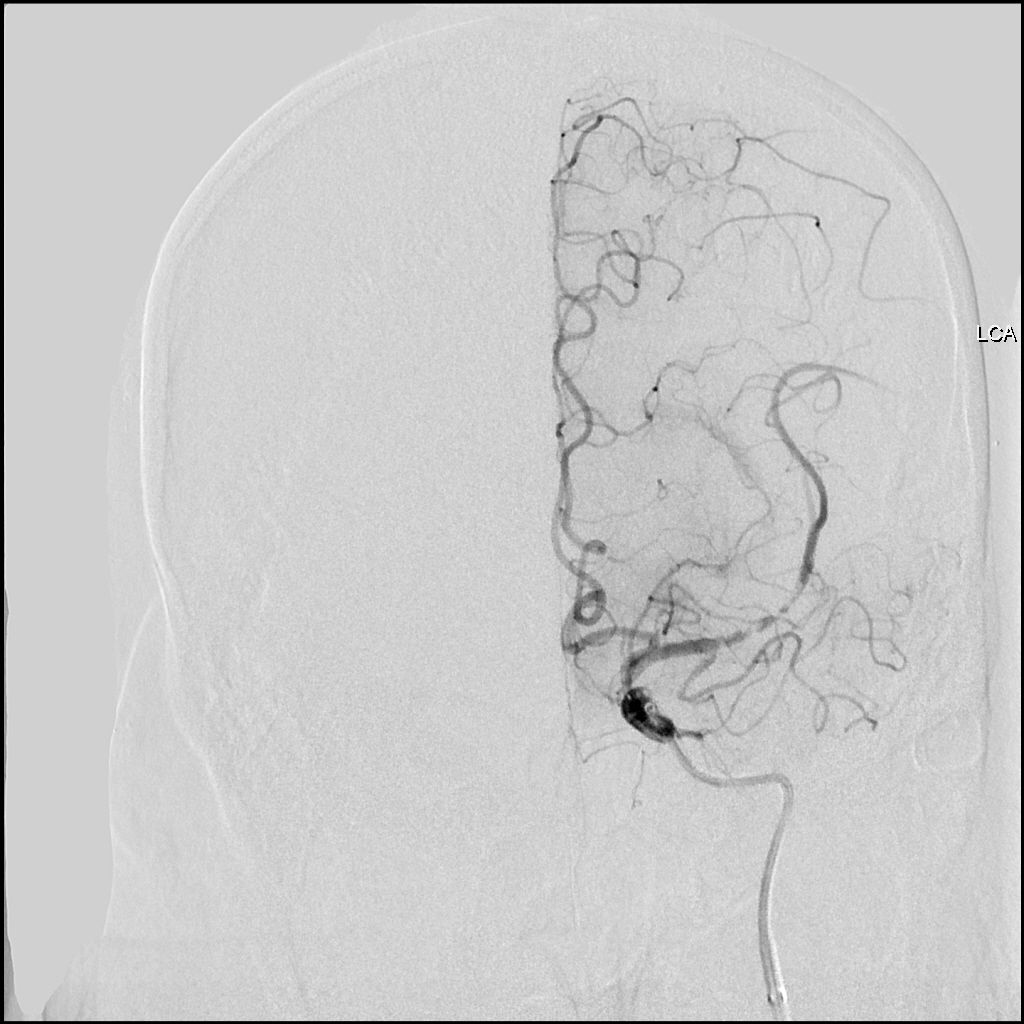

图2 CTA显示左侧大脑中动脉M1段闭塞

图4 单弯造影管进入左侧颈总动脉后造影:LM1段闭塞